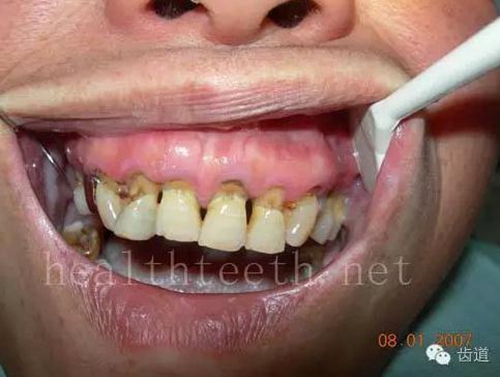

牙周大量牙石堆積

13.jpg